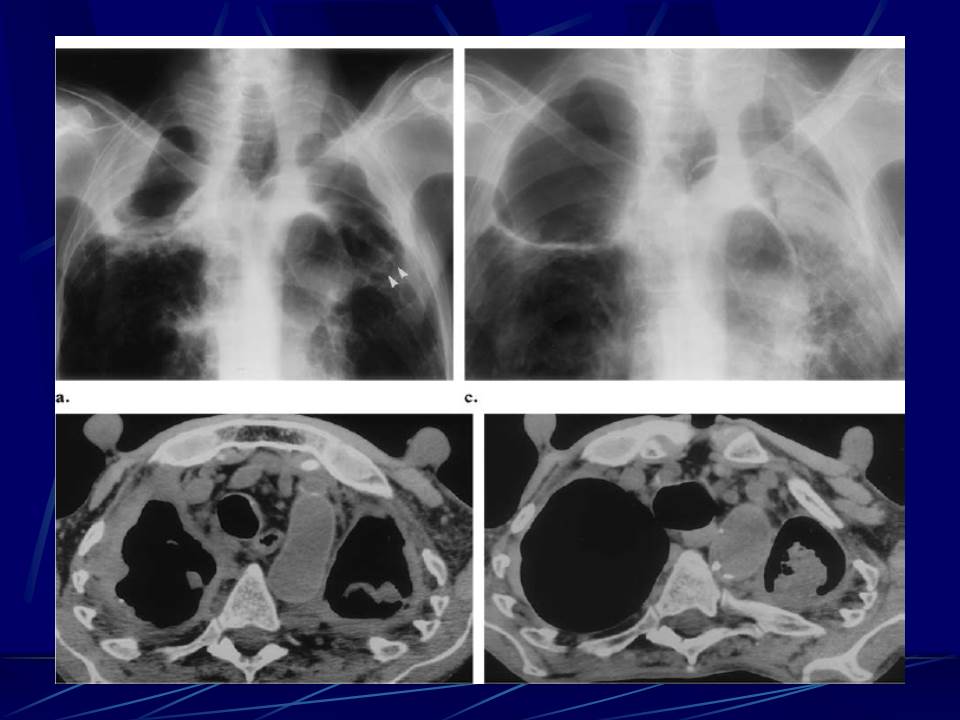

肺部真菌感染影像学分析